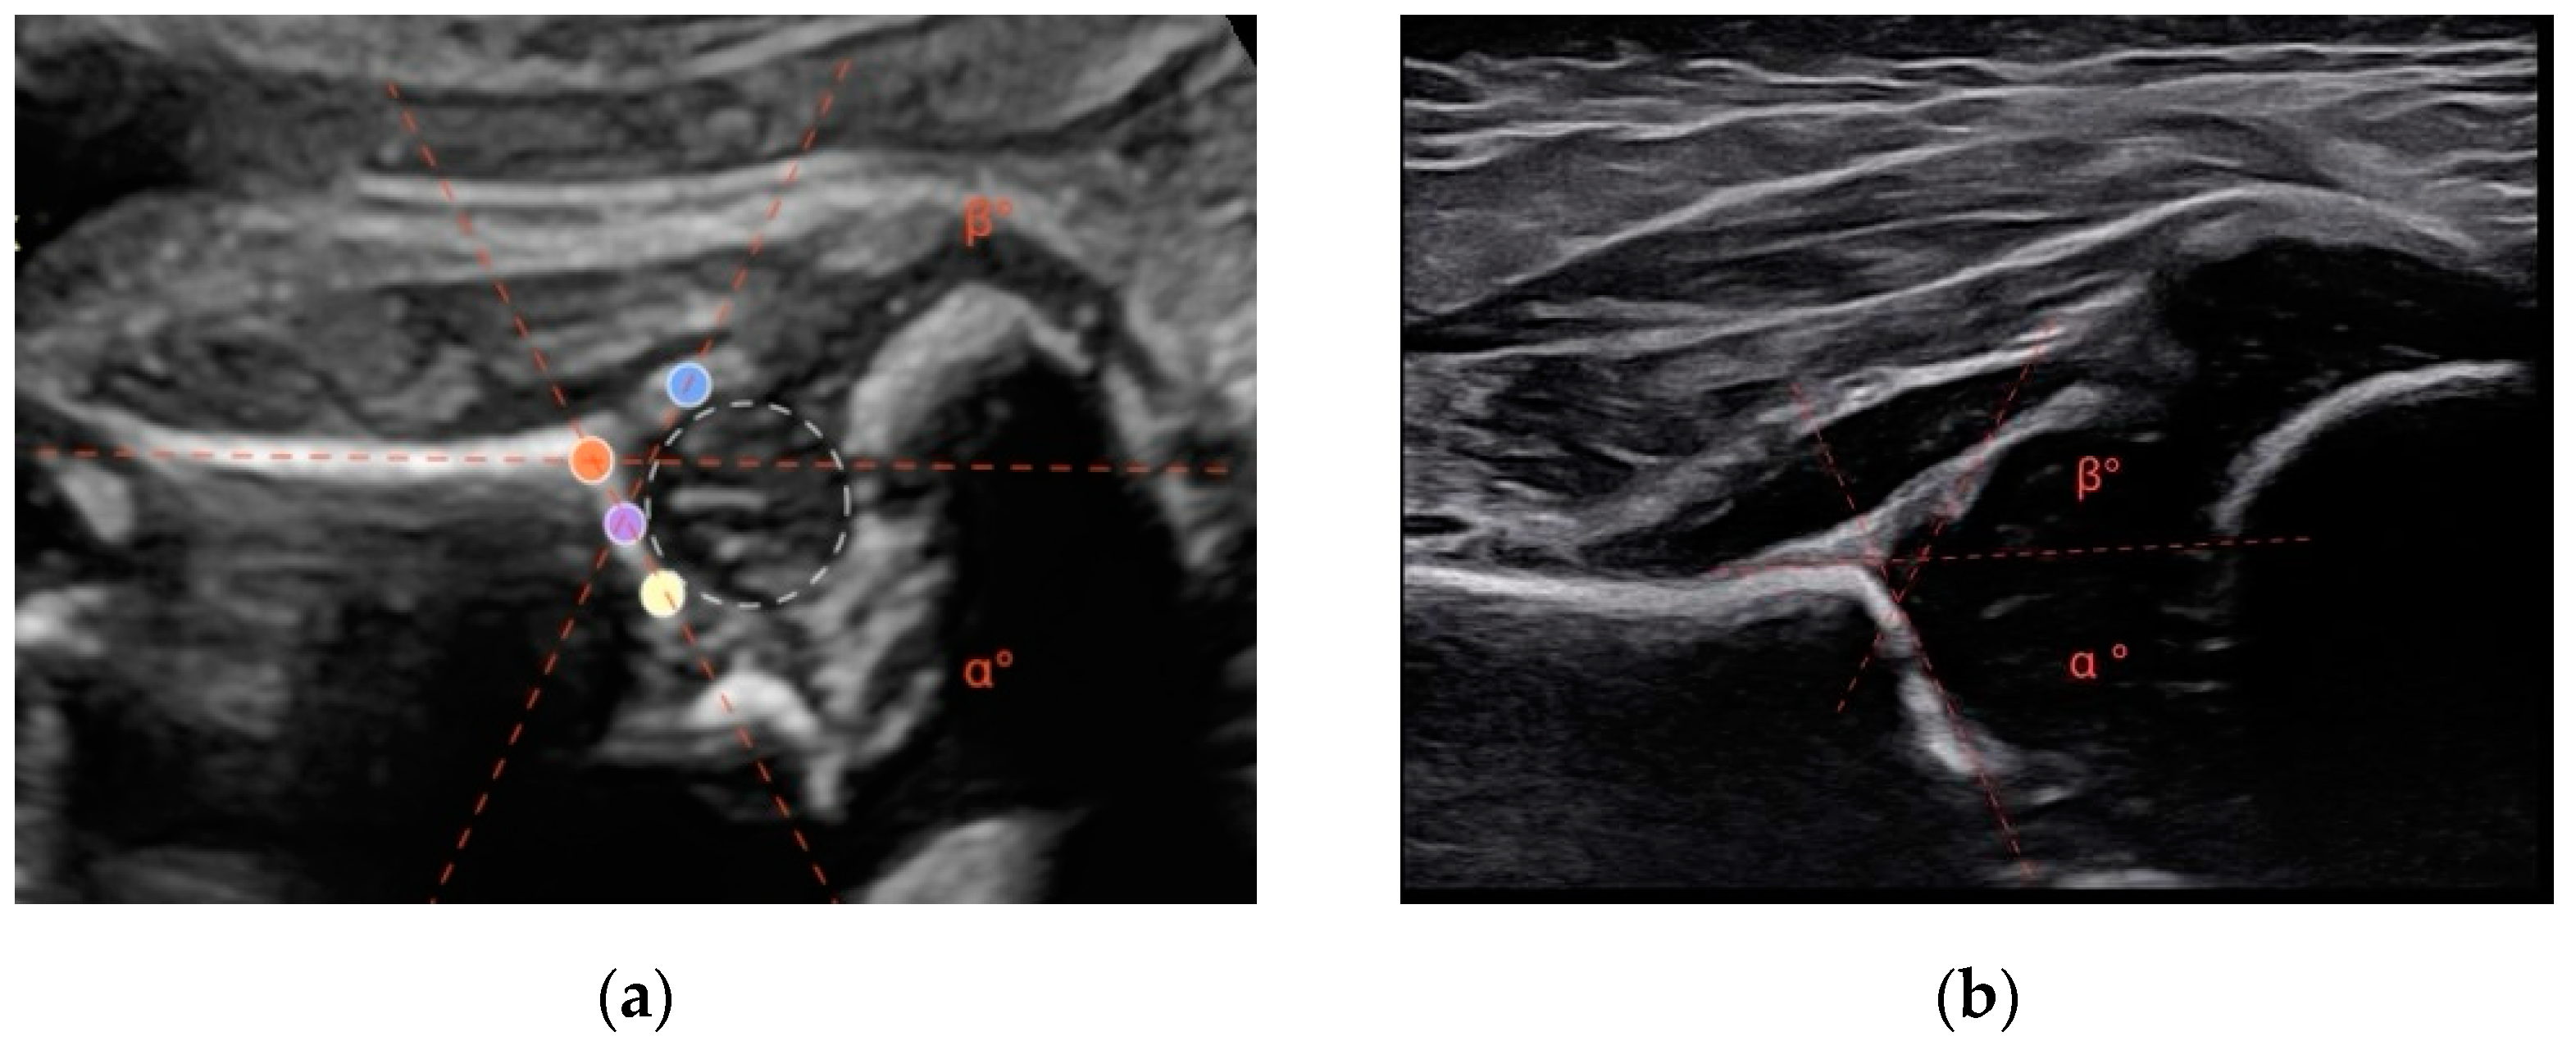

A modified Graf method was performed. This involves acquiring a lateral scan of the newborn’s hip. Similarly to the Graf method for infants, the alpha angle is defined as the angle formed between a line tangent to the iliac wing and a line tangent to the bony roof. The beta angle is formed by the line tangent to the iliac wing and a line tangent to the cartilaginous roof [9,11] (Figure 1).

(a) During the ultrasonographic examination of a 34-week-old fetus, the hip near the maternal abdominal wall was visualized. The acetabular roof (orange), the turning point (purple), the lower edge of the ossified ilium (yellow), and the labrum (blue). The angles alpha and beta are determined by the intersection of the lines connecting the specified reference points. In this case, the alpha angle measures 61°, while the beta angle measures 64°. (b) The same patient, in the postnatal ultrasound at 6 weeks of age, shows an alpha angle of 65° and a beta angle of 60°.